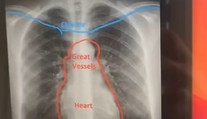

Tínedžerku (19) dlhšie trápil kašeľ. Následné röntgenové vyšetrenie odhalilo nečakanú anomáliu Róbert Ďurkáč 21. 7. 2021